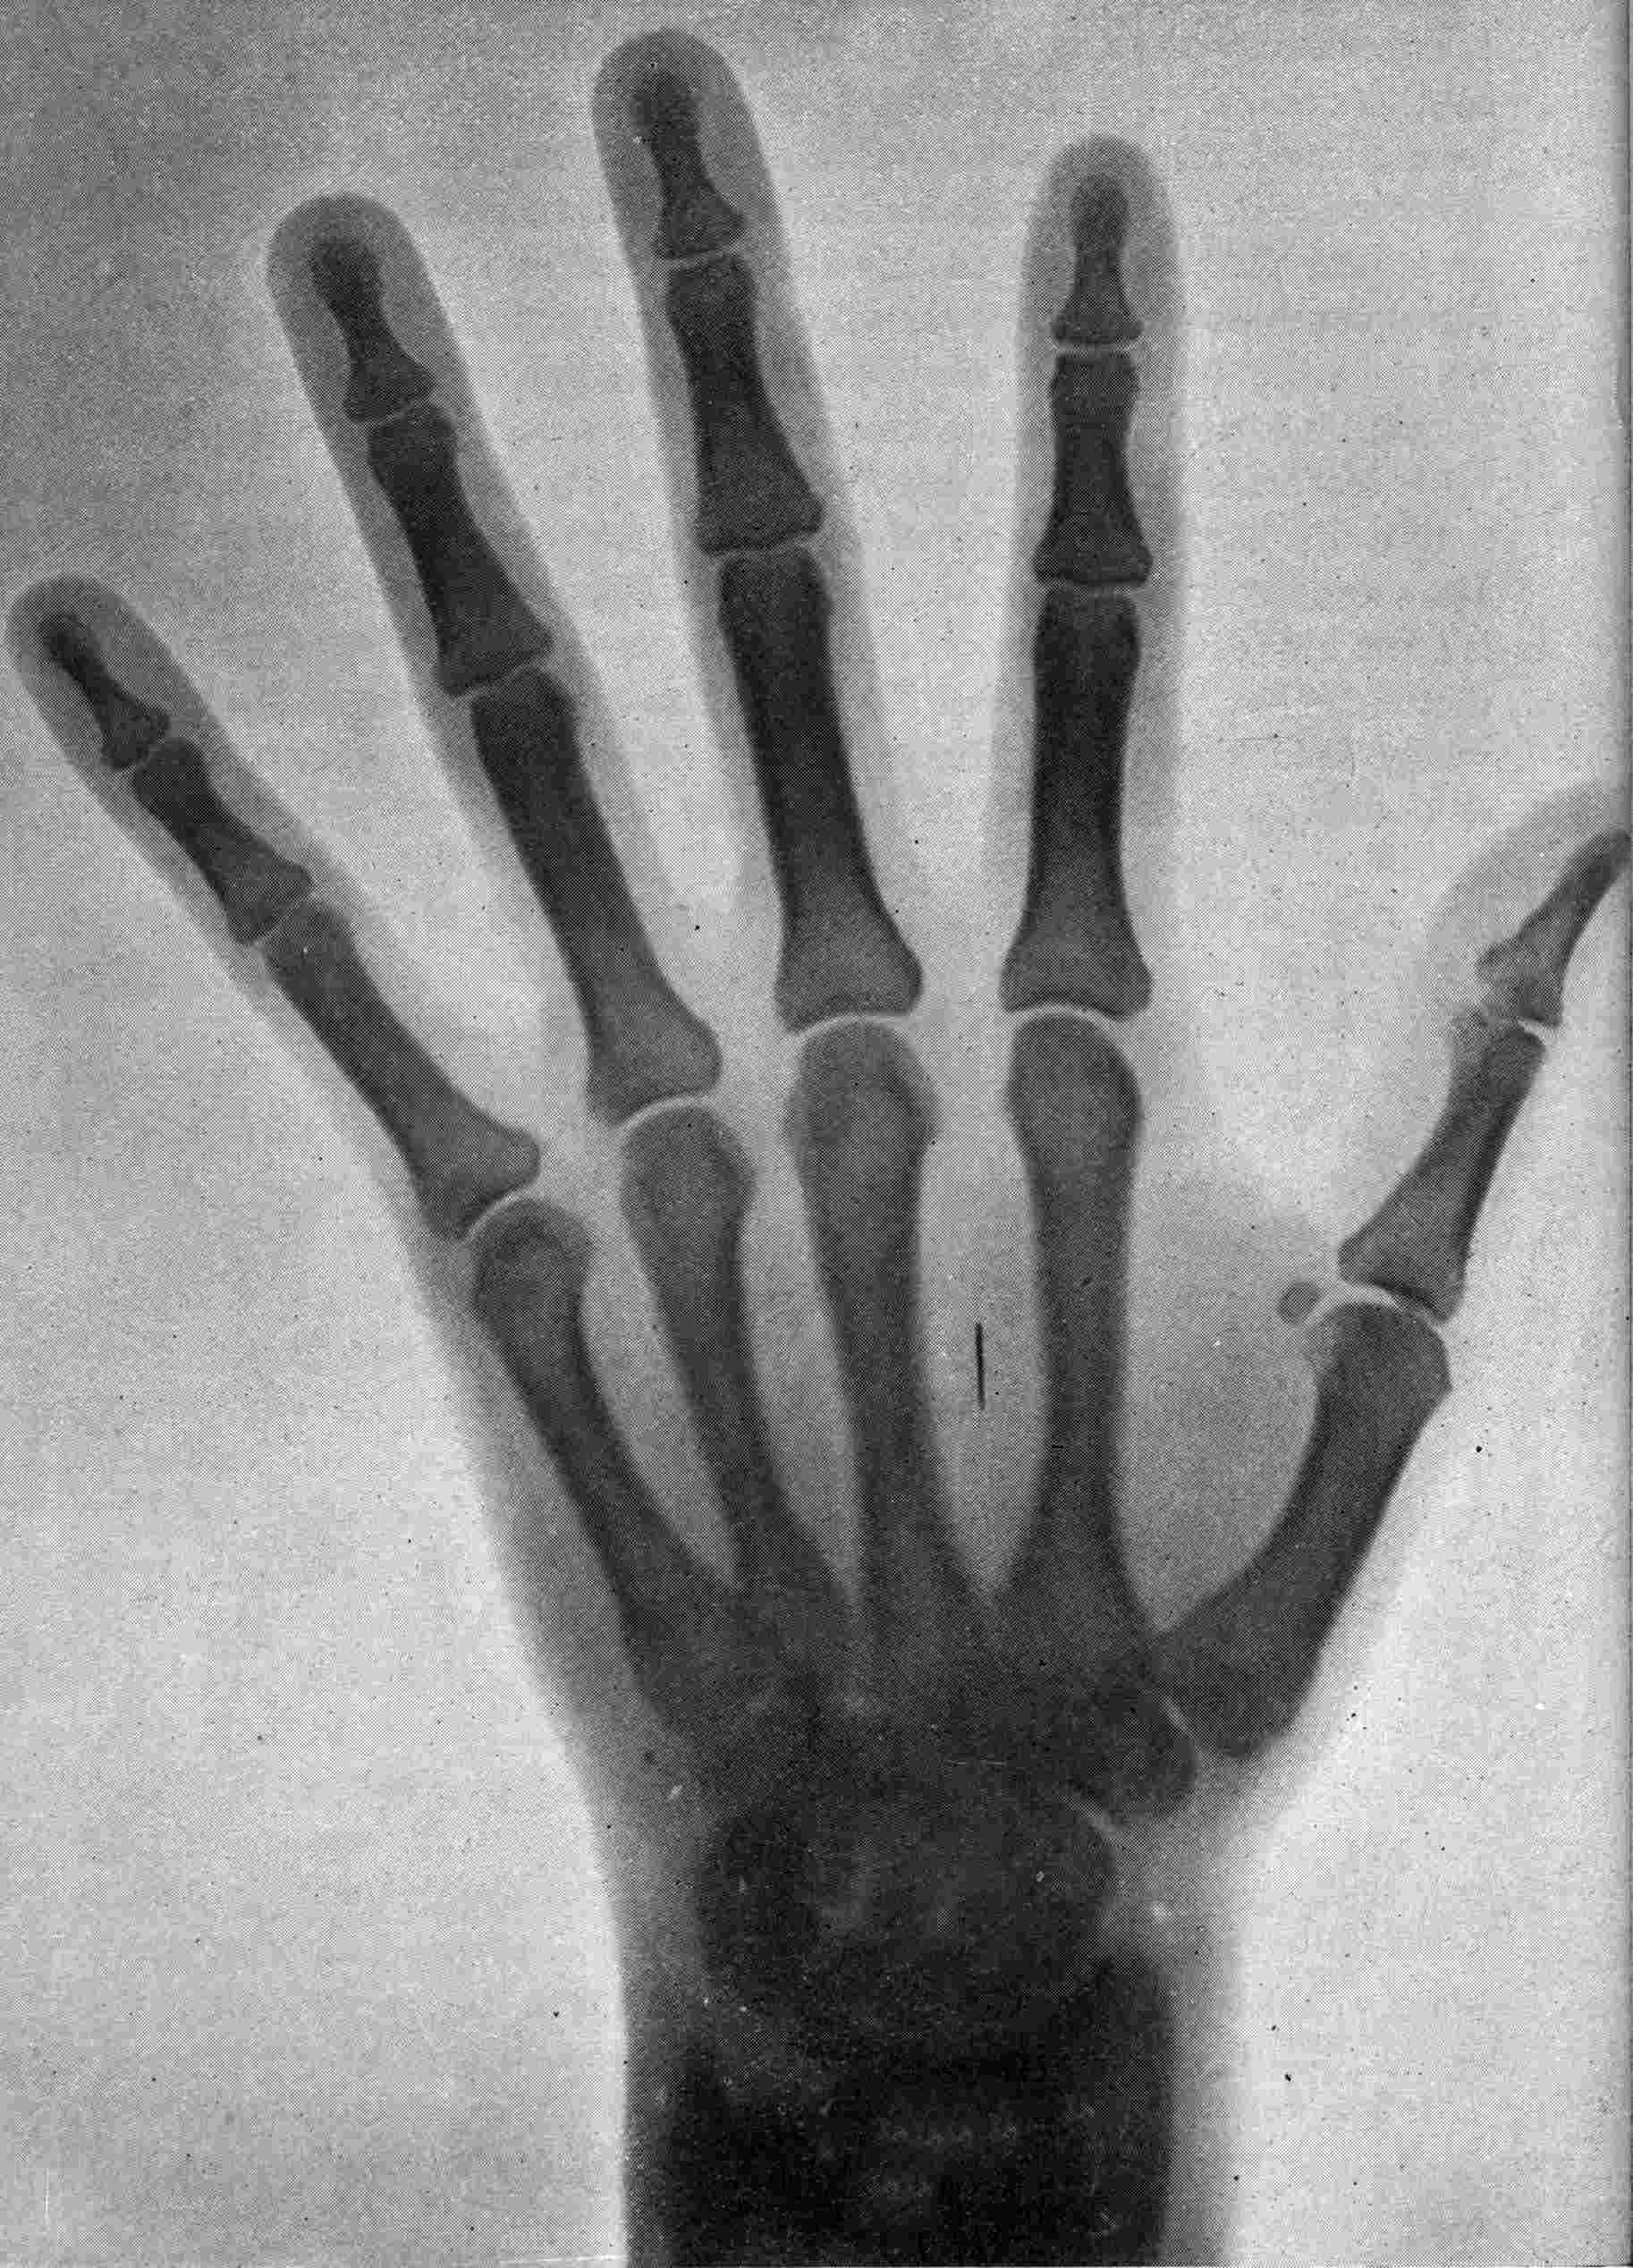

Fig. 1.—Head.

FROM SCIAGRAPHS BY PROF. DAYTON C. MILLER. § 204.

117. Transposition of Phosphorescent Spot and of Cathode Rays without a Magnet. Salvioni, Elster, Geitel, and Tesla